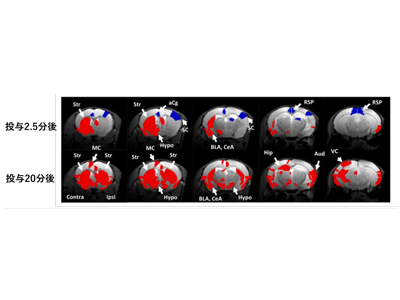

ホルマリンによる急性疼痛で、扁桃体・大脳皮質・視床を含む領域が5分以内に活動変化

まずZTEで神経活動を計測できることを確認するため、マウスの足裏に電気による感覚刺激(10Hz、2mA)を加え、大脳皮質体性感覚野の信号変化を調べた。次に、マウスの右足の裏にホルマリン(5%)を投与し、急性疼痛を引き起こした。ZTEで撮像開始から5分後にホルマリンを投与し、その後35分間撮像した。ZTEは3秒ごとに全脳の画像を取得した。コントロールとして生理食塩水を投与し、生理食塩水群の平均の信号に対してホルマリン投与による信号の比を計算した。

マウス足裏への感覚刺激により、大脳皮質体性感覚野の活動を確認した。次に、ホルマリン投与により、投与後5分以内に扁桃体、大脳皮質、視床を含む領域に活動変化が認められた。さらに投与後20分後に再びこれらの領域を含むより多くの領域に活動変化が認められた。この2相性の活動変化は、行動学の解析による2相性の急性炎症と時相的に合致していることから、急性炎症により生じる脳活動変化を反映している可能性が示唆される。